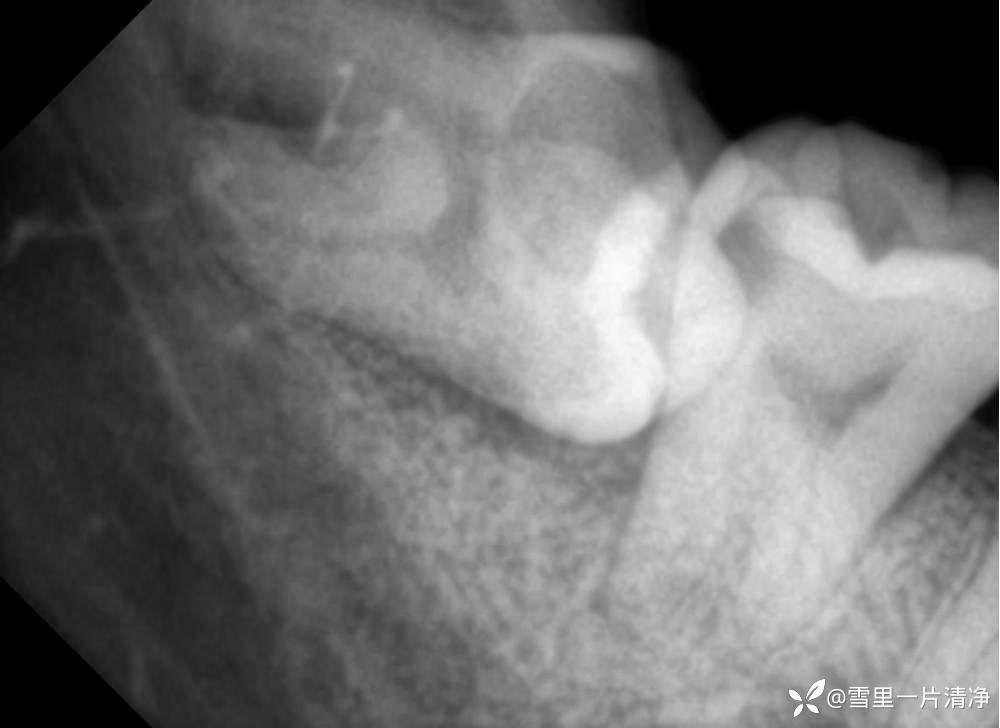

这里留个简单的片子你们可以发挥下想象你遇到了该怎么办